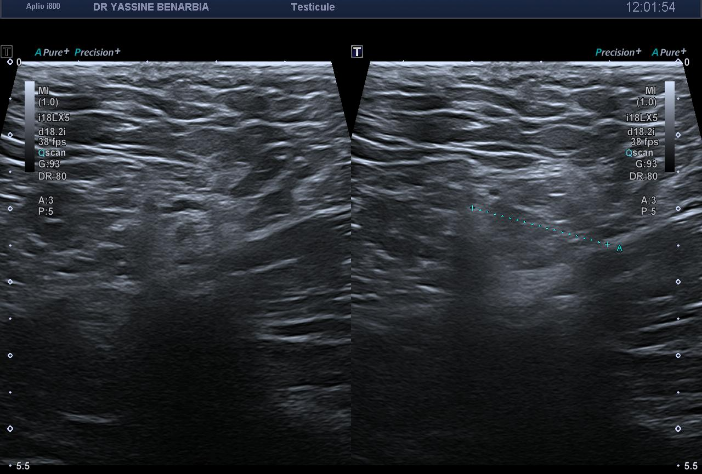

L'exploration de la région inguinale est donc réalisée révélant une hernie inguinale gauche indirecte avec un sac herniaire contenant des anses grêliques lors des manœuvres de Valsalva. Le collet herniaire mesure 20 mm lors de l'hyperpression abdominale. La hernie est parfaitement réductible et ne présente aucun signe de complication (péristaltisme conservé, paroi digestive fine, vascularisation normale au Doppler).

Il s'agit donc d'une hernie inguinale gauche indirecte non compliquée responsable de la symptomatologie douloureuse testiculaire.